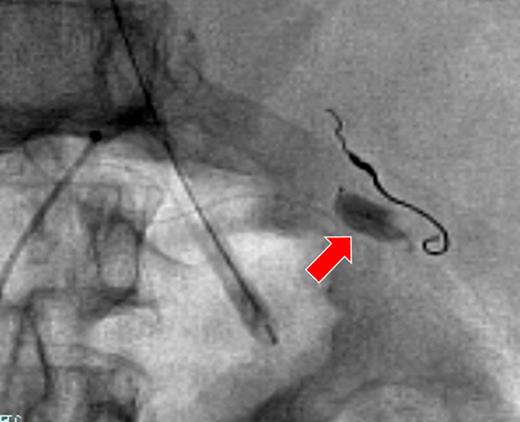

A 66-year-old man presented after suffering sudden hypotension and abdominal distension, followed by a rapid and progressive anemia. After arriving at hospital, he collapsed and went into cardiac arrest. Return of spontaneous circulation occurred after 36 min of cardiopulmonary resuscitation and rapid blood transfusion. Abdominal contrast-enhanced computed tomography (CECT) revealed a large hematoma around the spleen and liver, in paracolic gutters and the pelvis with active arterial extravasation and apparent capsular disruption (Fig. 1). He was transferred to our hospital for definitive, emergency hemostasis. At admission, his systolic blood pressure (BP) was 90 mmHg; heart rate (HR), 80 bpm; hemoglobin (Hb) level, 6.7 g/dl; hematocrit (Ht), 19.0%; prothrombin time-international normalized ratio (PT-INR), 2.16 and activated partial thromboplastin time (APTT), 63.9 s (under massive transfusion). He was currently on warfarin therapy for anticoagulation following a total aortic arch replacement including aortic valve replacement at the age of 60. He presented with no history of trauma, and Moraxella catarrhalis had been detected in a blood culture taken on initial presentation. We made a diagnosis of ASR secondary to infection exacerbated by anticoagulation therapy. We first planned to perform a splenectomy as a definitive hemostatic treatment. However, his transfusion requirement was massive and the risk of significantly worsened hemorrhage during any operative procedure was increased by his iatrogenic coagulopathy. After discussion with surgery team and interventional radiology (IR) team, transient occlusion of the splenic artery using a microballoon catheter was performed (LOGOS, Piolax, Inc., Kanagawa, Japan; arrival to occlusion, 90 min; arrival to angiography suite, 60 min; procedure time to occlusion, 15 min; Fig. 2). Soon after balloon occlusion, the patient's hemodynamic state improved and his anemia stabilized. Perioperatively, 6 units of red cell concentrate (RCC) and 10 units of fresh frozen plasma (FFP) were transfused. The patient's coagulopathy improved on hospital Day 2 (Ht, 25%; PT-INR, 1.35 and APTT, 33.5 s) and was taken to the operating theater for open splenectomy. The spleen was swollen and capsular rupture was indeed identified, but there was no finding of a solid tumor or abscess formation. Bone marrow aspiration did not reveal any evidence of a hematological disorder. There was no subsequent hemorrhage postoperatively. He was extubated on Day 4, and was discharged from the ICU on Day 6. The patient was transferred to another hospital on Day 25 without residual deficits or complications from his cardiac arrest.

The right gastroepiploic artery with platinum coils after embolization. The microballoon catheter was placed in the splenic artery (arrow).